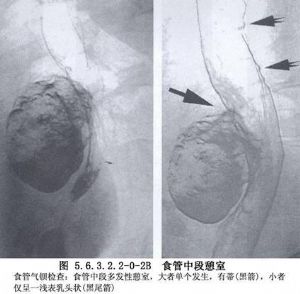

食管中段憩室的诊断主要依靠食管钡餐造影检查和内镜检查。在做钡餐造影检查时,患者取头低脚高位或俯卧位,或取左侧卧位,憩室的位置和轮廓容易显示。必要时做食管CT检查和食管功能测定,以除外其他较严重的疾病。如果出现慢性肺化脓症的症状,则有必要做气管镜检查和肺CT扫描,以明确肺部病变的范围。如怀疑有憩室-支气管瘘,须做支气管碘油造影或气管镜检查;内镜检查有助于发现瘘口。嘱患者口服亚甲蓝或其他染料,若在痰中发现蓝色,即可以确诊(图5.6.3.2.2-0-1~5.6.3.2.2-0-4)。